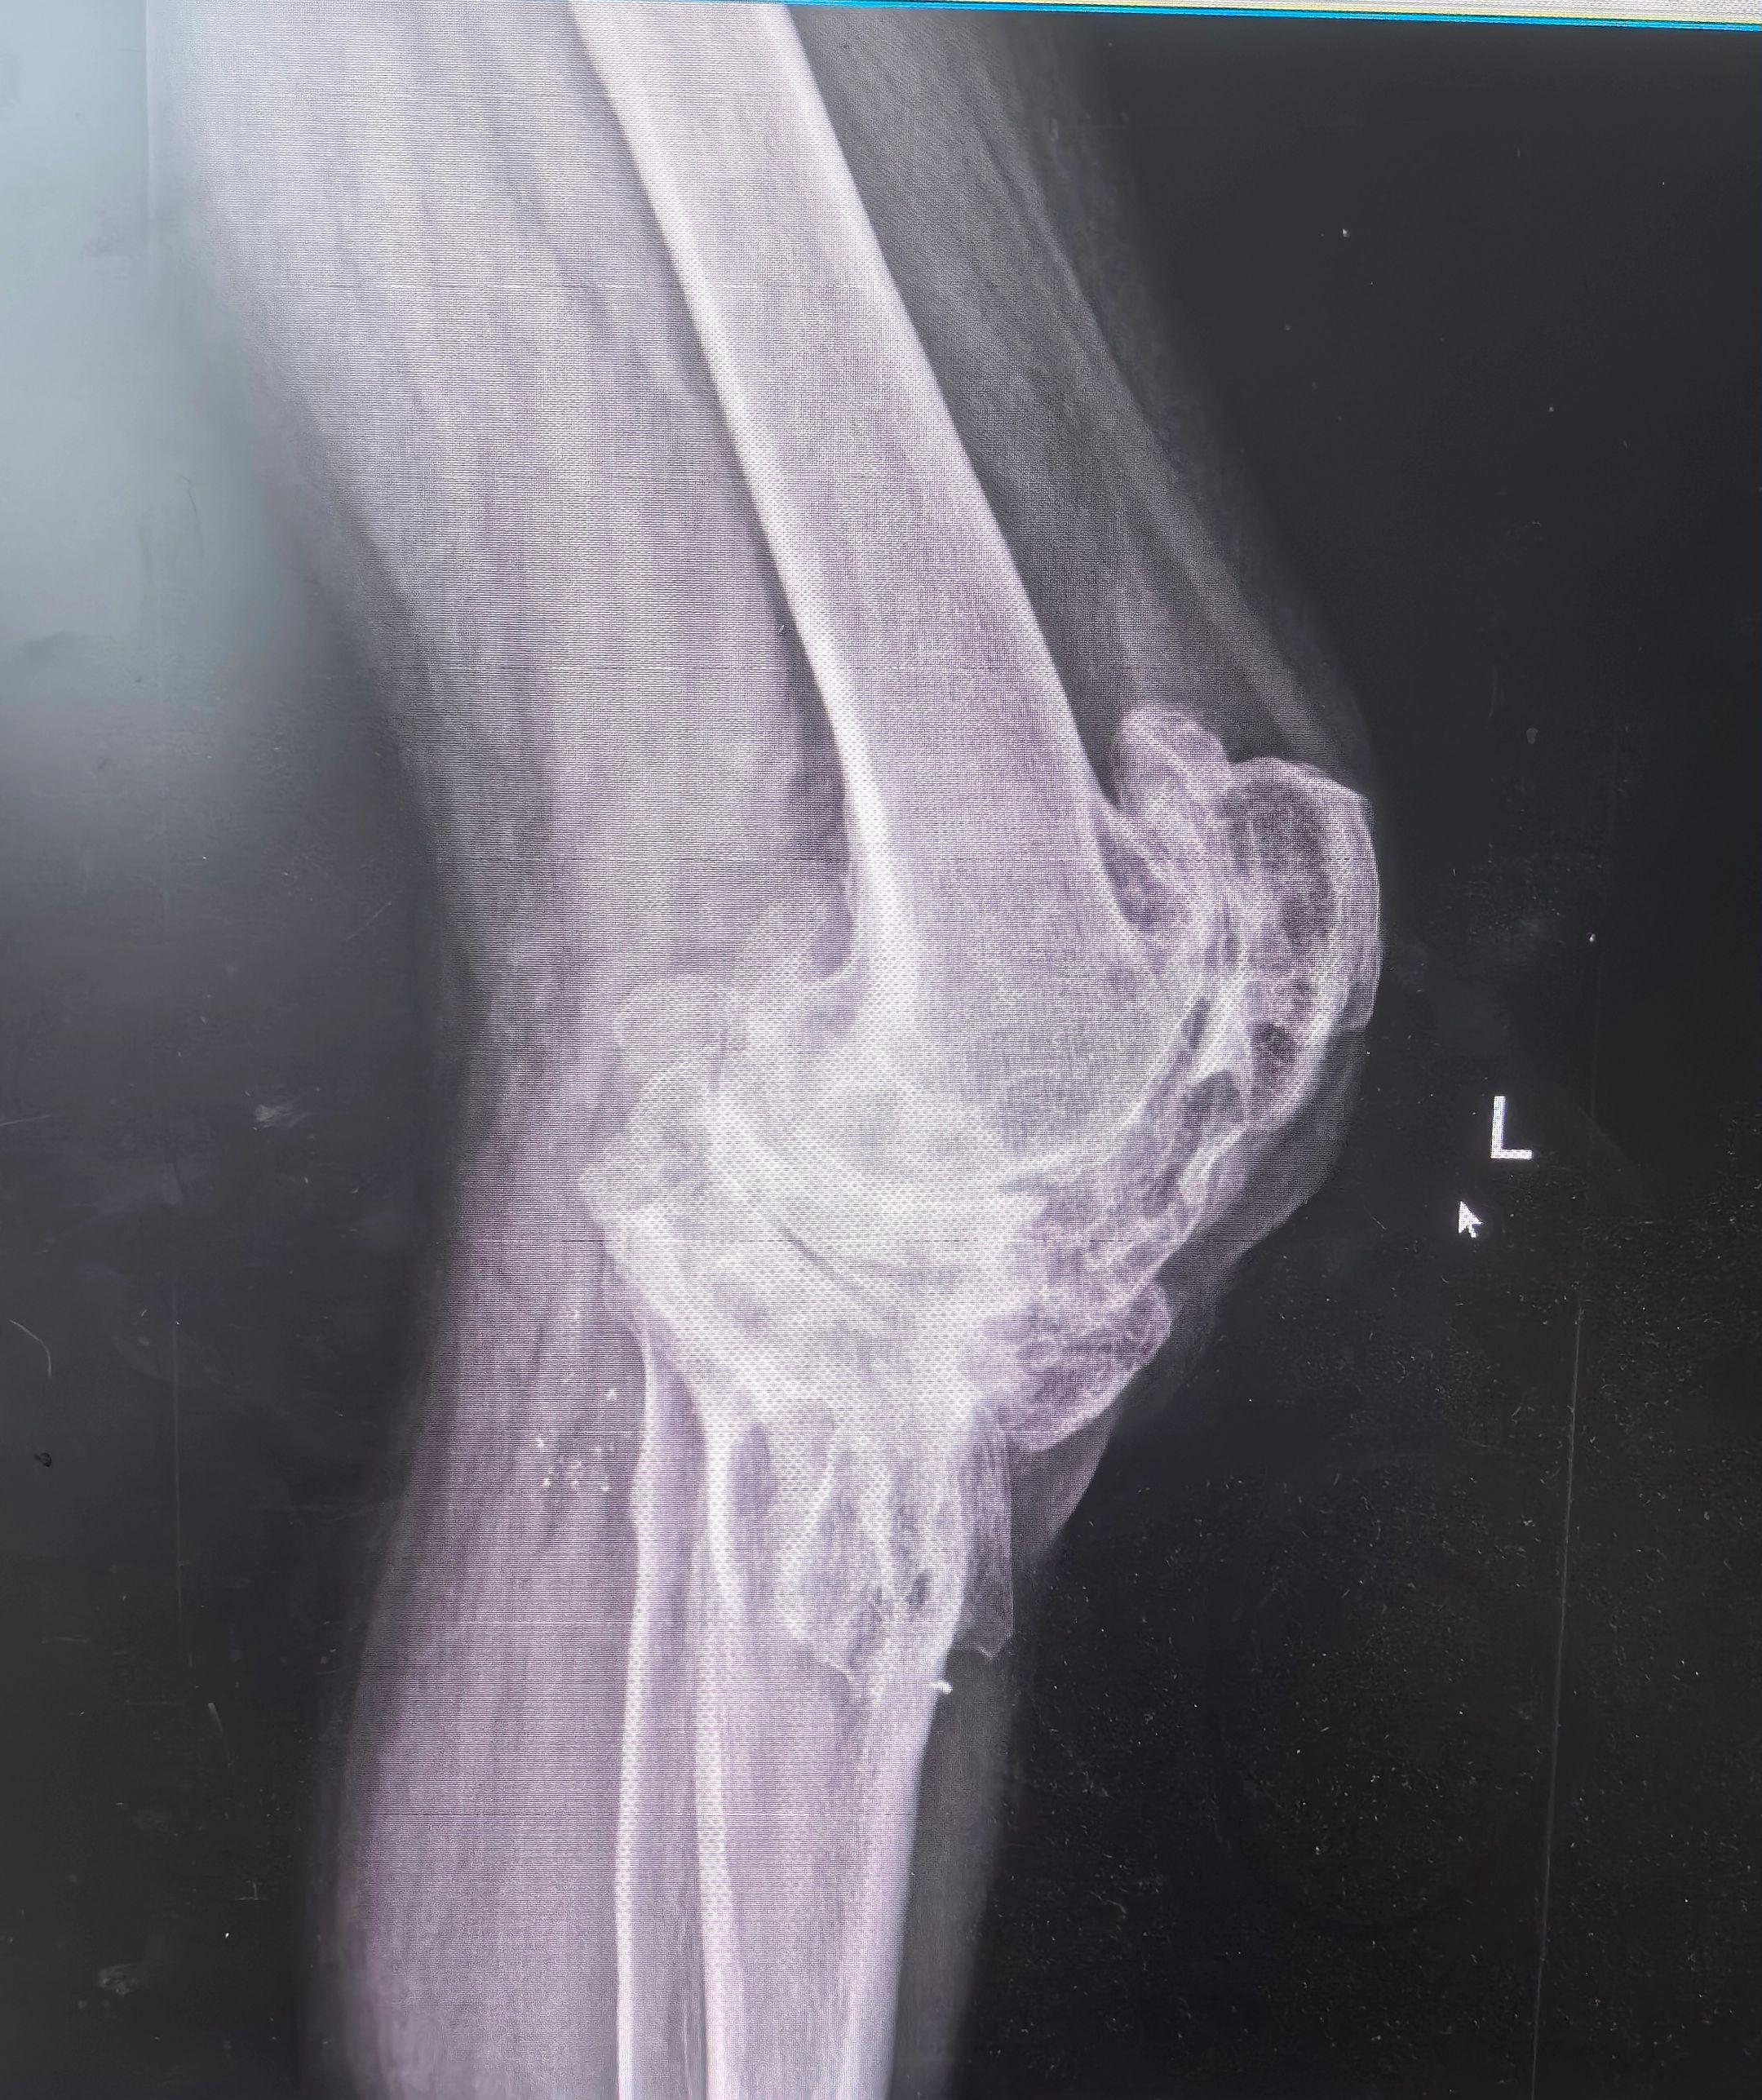

创伤性关节炎,膝关节置换。19岁胫骨平台骨折畸形愈合,未处理,现52岁,重度创伤性膝关节炎,疼痛,无活动度,行走困难。各位老登,怎么破?铰链膝?CCK?定制膝?